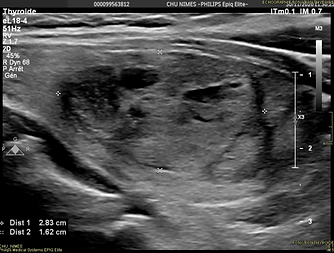

Paciente de 39 años con nódulo ístmico derecho de gen local sin anormalidad biológica

benigno en citología dos veces, termoablación por gen local y negativa a cirugía

Hospital Universitario de Nîmes, Dr. Haitham Sharara

Control 4 meses post RF disminución volumétrica 88%